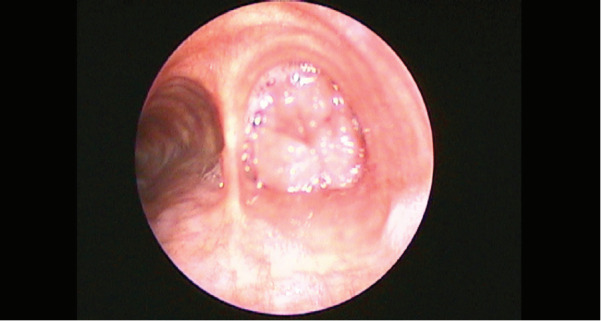

Endobronchial solitary papillomas are extremely rare lung neoplasms originating from the bronchial surface epithelium. They often present with cough or recurrent hemoptysis. These tumors are benign, but they should be followed closely because they may even have a low probability of malignant transformation features. It should be kept in mind that malignancy may develop especially if the patient is a smoker. Although the etiology is not known for certain, it is thought to be caused by human papillomavirus in some cases. A 43-year-old male patient was admitted with a complaint of chronic cough. Rigid bronchoscopy was performed for diagnostic and therapeutic purposes after imaging techniques revealed a lesion obstructing the lumen of the right main bronchus. The pathology result was reported as mixed bronchial papilloma. We aimed to present our case because of its rarity and to indicate that chronic cough must be further evaluated.

Abstract Image